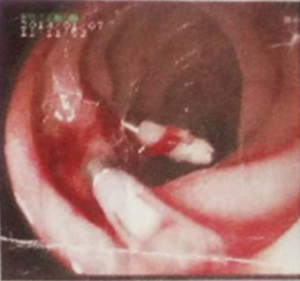

The patient, a 33-year-old woman without family history, had bleeding diathesis since childhood with consequent recurrent gastrointestinal bleeding for 7 years (Figure 1). Between 2 and 12 years of age, she suffered recurrent nosebleeds which eventually led to anemia, and at the age of 5 years, received a transfusion of 200 mL of blood for anemia. During her first menstrual period at the age of 12 years, she experienced prolonged uterine bleeding which was treated by dilation and curettage and a transfusion of 1,200 mL of blood. Thereafter, she suffered chronic heavy menstrual bleeding. Between 19 and 28 years of age, she had five occurrences of corpus luteum rupture treated twice by laparoscopy and three tines conservatively. To identify the underlying mechanism of chronic recurrent anemia and bleeding diathesis, she underwent bone marrow aspiration and biopsy three times between 26 to 28 years of age, the results of which all indicated active bone marrow proliferation. Iron-deficiency anemia was then suspected, and long-term iron supplementation was adopted for treatment. The patient’s hemoglobin level reached as low as 38 g/L when most severe with black stools, which, however, were overlooked by the patient and doctors due to the use of iron supplements. At the age of 29 years, she had a sudden onset of massive tarry stools and was admitted to the emergency department where a gastroscopy was performed for the first time and revealed a 0.4 cm ×0.4 cm ring-shaped ulcer that oozed blood on the surface in the descending duodenum. According to the patient’s recollection, although she could not remember the accurate hemoglobin level of that time, she had severe anemia. Diagnoses of descending duodenum ulceration or Dieulafoy’s lesion were considered by the attending gastroenterologist as causes of bleeding, and titanium clips were used for hemostasis (Figure 2), Biopsy was not performed considering the active phase of bleeding. Helicobacter Pylori test was negative. After the patient’s condition improved, she was discharged and continued taking proton pump inhibitors afterward, but the stools remained black even if with normal steady hemoglobin levels. At the age of 30 years old, a massive digestive tract bleeding reoccurred, and a second gastroscopy showed erosive lesions in the descending duodenum as the hemorrhagic foci. Again, arteriovenous malformations of the descending duodenum or Dieulafoy’s lesion were considered by the attending doctor as causes of bleeding, and lauromacrogol injection was administered for the treatment of angiosclerosis. Despite temporary improvement of bleeding after treatment, black stools soon recurred and caused severe anemia, which brought the patient to the Department of Gastroenterology of Chinese PLA General Hospital in August 2018.